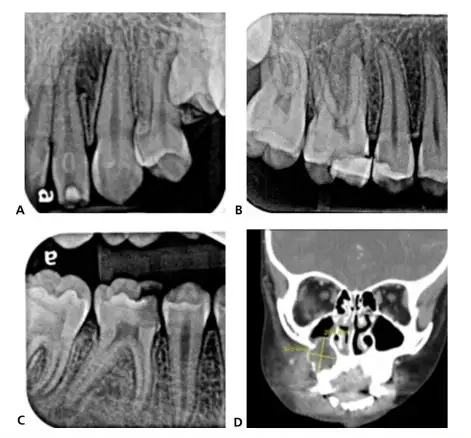

In a report published in June 2025 in the Journal of the American Dental Association, researchers reviewed 201 pediatric cases of facial cellulitis of odontogenic origin (FCOO)—a severe infection often stemming from untreated tooth decay—and found that children without a regular “dental home” experienced more complex, intensive treatment courses than those with one. A dental home is defined as the ongoing relationship between a dentist and a patient, focusing on comprehensive, accessible, and coordinated oral health care.

Nearly half of the patients (48%) did not have an established dental home, and almost one in four had never seen a dentist before their infection. Younger children and those with special healthcare needs were more likely to require hospitalization, sedation, or general anesthesia. The study found that untreated cavities caused more than 70% of cases, while failed dental restorations accounted for another 22%.